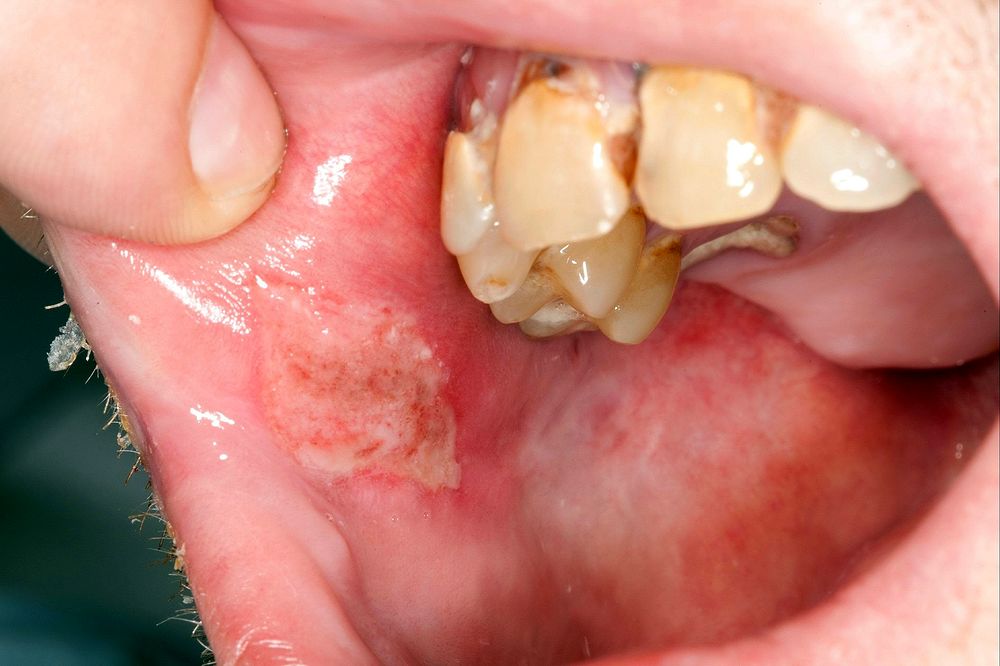

ORAL MEDICINE : Oral lesions and diseases associated with them

The mouth is frequently involved in conditions that affect the skin, but it is also affected by many systemic diseases.

Oral involvement may precede or follow the appearance of findings at other locations.